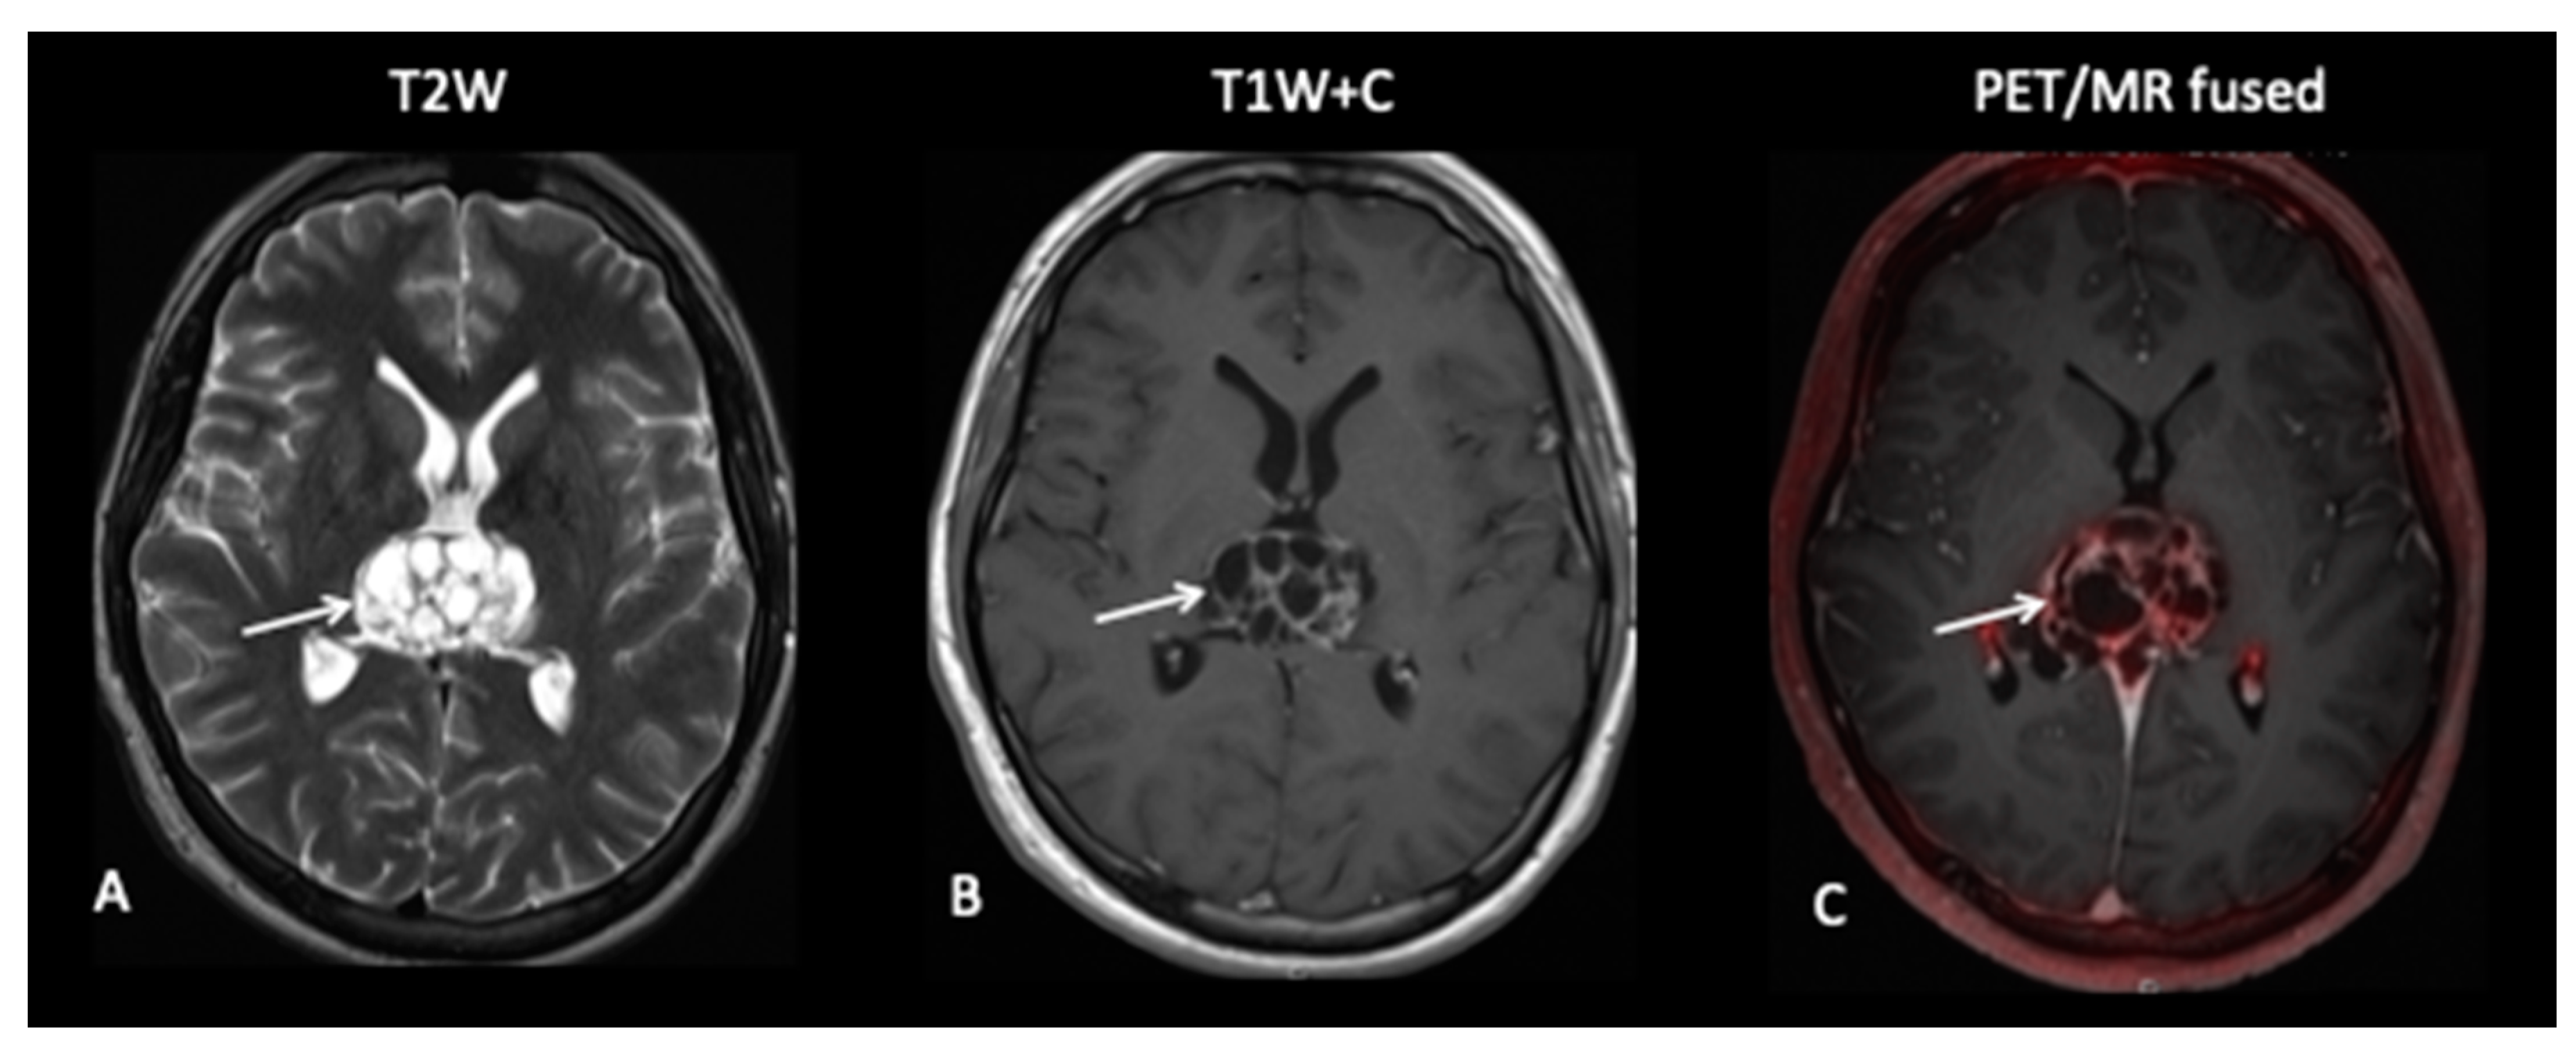

- Patient 8: Suspicion of Transformation

A 15-year-old female with known low-grade glioma during routine surveillance was noted to have developed a large lesion in the corpus callosum. This occurred 7 years after her initial diagnosis of an optic pathway tumour. The MRI scan raised the possibility of malignant transformation to high-grade glioma. FDOPA (Figure 11) discounted the possibility of transformation as the FDOPA uptake within the corpus callosal lesion was low intensity, unlike that seen in high-grade gliomas.

Figure 11.

MRI demonstrates an expansile lesion in the right aspect of the splenium (A), which demonstrates heterogenous enhancement (B), suspicious for malignant transformation. However, FDOPA (C) did not demonstrate increased uptake, and the lesion was considered low grade.